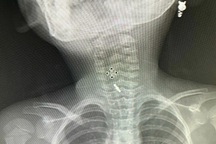

Kết quả chụp X-quang, các bác sĩ phát hiện một đồng xu có kích thước 3-4cm trong dạ dày của bệnh nhi.

Do bệnh nhi đang trong tình trạng viêm phổi, các bác sĩ đã ưu tiên điều trị ổn định đường hô hấp. Sau khi sức khỏe của bé D. ổn định, bác sĩ đã nội soi gây mê và gắp đồng xu ra khỏi dạ dày một cách an toàn, không để lại biến chứng nào.